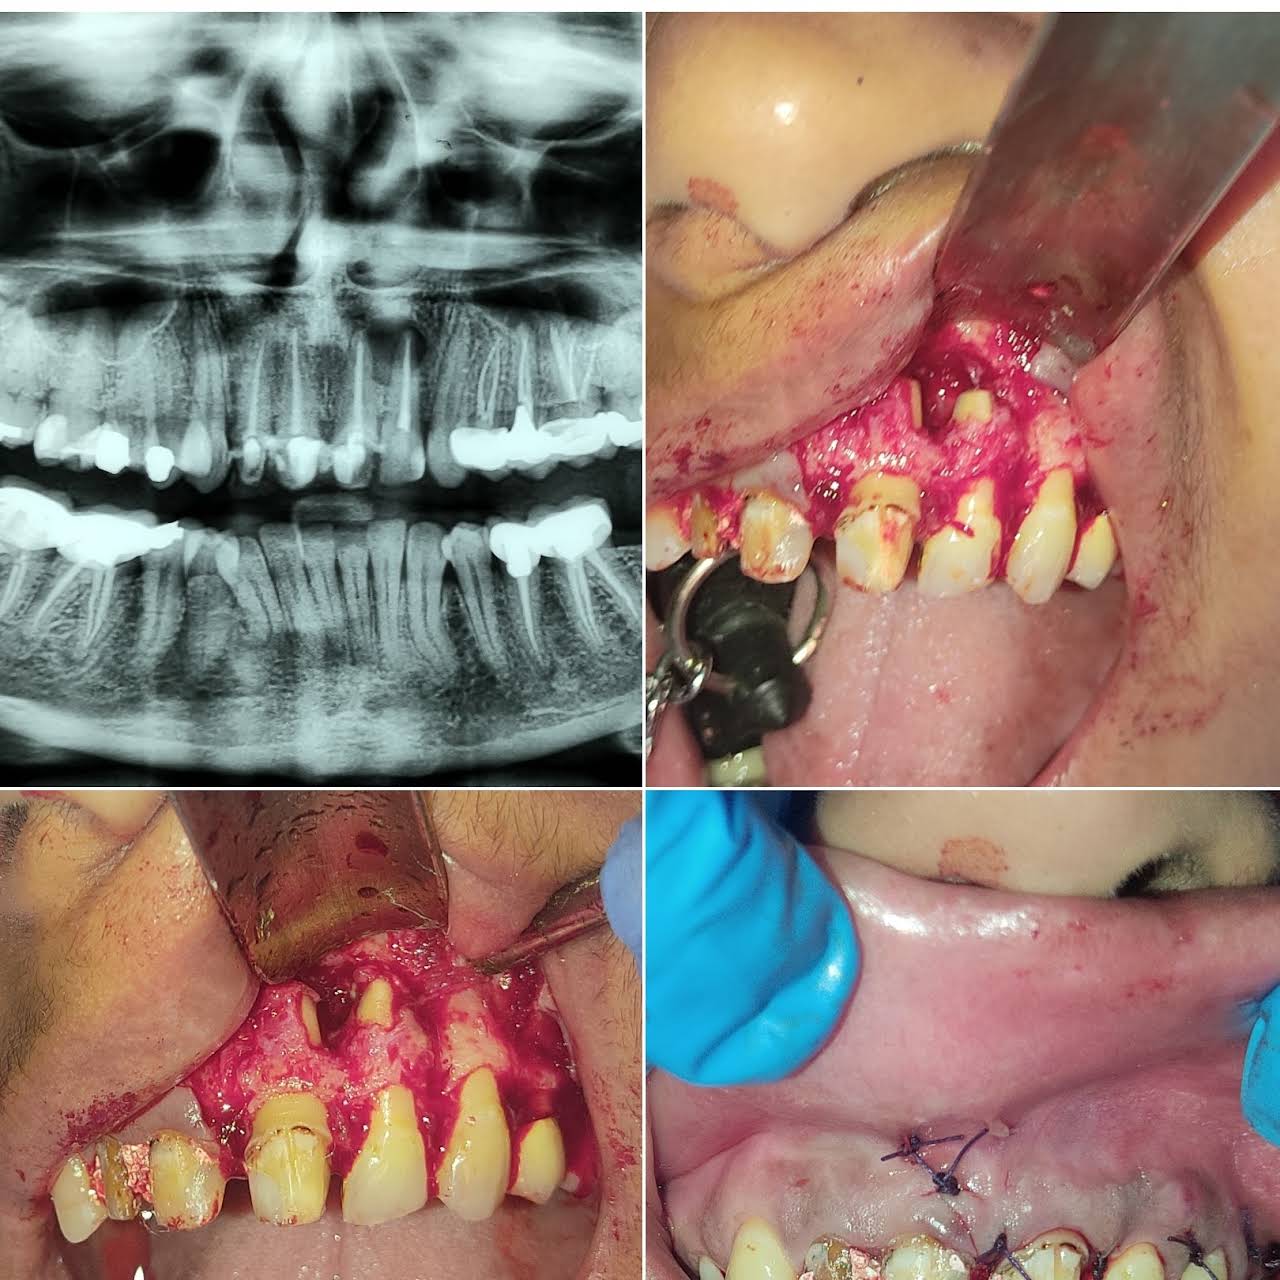

Oral & Maxillofacial Surgery

Oral and maxillofacial surgery is a surgical specialty focusing on reconstructive surgery of the face, facial trauma surgery, the oral ca ...